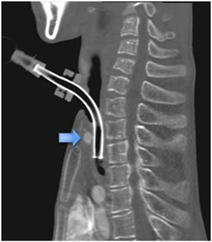

(1)気管切開とは

気管とその上部の皮膚を切開してその部分から気管にカニューレを挿入する気道確保の方法です。

気管切開をした上で人工呼吸器を使う場合もあります。。

B気管カニューレ

気管切開後に切開部から気管内に挿入するものを気管カニューレといいます。

気管切開後の気道確保、気道分泌物の吸引などのために使用します。

補足:合併症---腕頭動脈瘻からの出血

1)腕頭動脈とは

大動脈弓から最初に分枝し、右の胸鎖関節の後ろで右腕への右鎖骨下動脈と、頭への右総頚動脈に2分枝するまでの

血管です。

腕(右鎖骨下動脈)と頭(右総頚動脈)へと繋ぐ動脈であることから、この名前が付いたとされます。

2)気管腕頭動脈瘻とは

胸郭扁平化を起こすと、腕頭動脈とカニューレに挟まれた気管前壁が、胸骨と椎骨の間で逃げ道を無くして長期の

動脈拍動で圧迫されて穿破する事があります。

腕頭動脈瘻の発生は0.7%位との報告があります。

出血による死亡率は40%、手術時死亡率は55.6% とされています。(Glman.1994、Jones.1976)